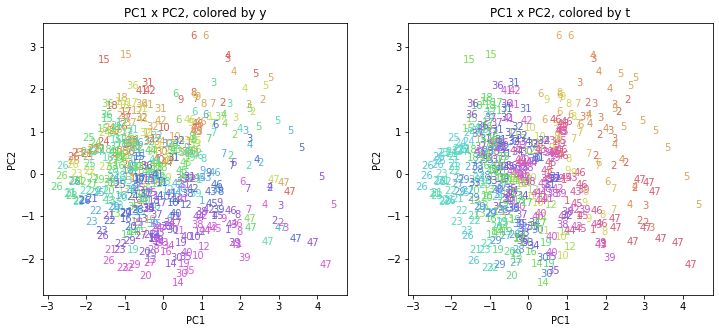

PCAの結果の第n主成分をPCnと表記します。

医療費データの場合と同様に、PCAの結果を見やすく表示するため、seabornのカラーパレットを使って、年月別、都道府県別に色分けして図示してみます(左側が年月別に色分け、右側が都道府県別に色分け)。PC1~PC8まで表示しました。

都道府県番号の表示

上の色分けだけでは都道府県が区別しにくいので、医療費データの場合と同様に、点の代わりに都道府県番号をプロットした図も描いておきます(色分けは上と同じ)。

医療費データの場合ほどはっきりとはしていませんが、PC2が概ね時間の経過を表す成分で、残りの成分が時点によって変わらない地域の特徴を表す成分となっているようです。

また、PC1×PC3を見ると、47沖縄が他の都道府県からかなり離れたところに位置しており、沖縄の地域差が際立っているのが分かります。これは、以前別の記事で年齢階級のない健診データでPCAを実行した場合と似た結果となっています。

今回は、医療費データと同様に、健診データ240次元についてPCAを実行してみました。PCAの結果、医療費データの場合ほどはっきりしとはしていませんが、第2主成分が概ね時間の経過を表す成分で、時間軸に沿った全体的な動き(全国的な動き)を表しており、それ以外の成分が地域の特徴を表す成分で、この10年間あまり変わっていないことがわかりました。

また、以前別の記事で、年齢階級のない健診データを使ってPCAを実行しましたが、それとも似た結果となりました。